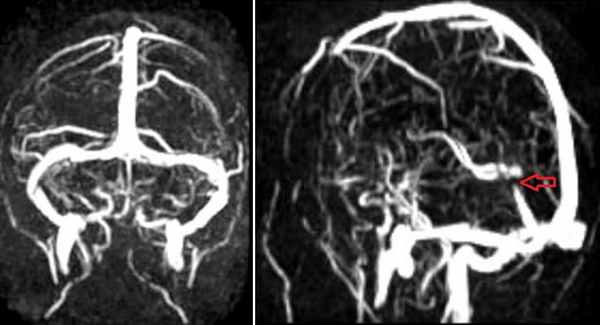

Тромбоз правого поперечного синуса – гипоинтенсивные участки по Т2 (внутриклеточный дезоксигемоглобин).

Для подтверждения тромбоза венозного синуса и определения точной локализации и протяженности тромба необходимо проведение МР-венографии.

МР-венография – отсутствие визуализации кровотока в правом поперечном синусе и яремной вене.

МР-венография: тромбоз правого поперечного синуса. Отмечается потеря МР-сигнала от правого поперечного синуса.

Наличие визуализации синуса на «сырых» данных или же МРТ головного мозга подтверждает тромбоз синуса и исключает его гипо- и аплазию.

Тромбоз правого поперечного синуса. Отсутствие феномена «пустоты потока» от правого поперечного синуса на МРТ головного мозга. Отсутствие визуализации правого поперечного синуса на МР-венографии.